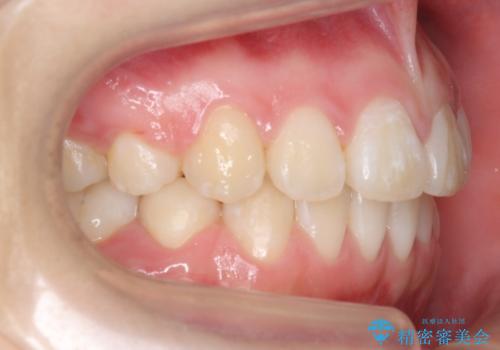

成人式に間に合う 前歯の矯正

- 前歯のがたがたを主訴に来院。

口元も下げたいとのことでした。

成人式の時に前歯が下がって、揃った状態で写真を撮ることができ、大変喜んでおられました。